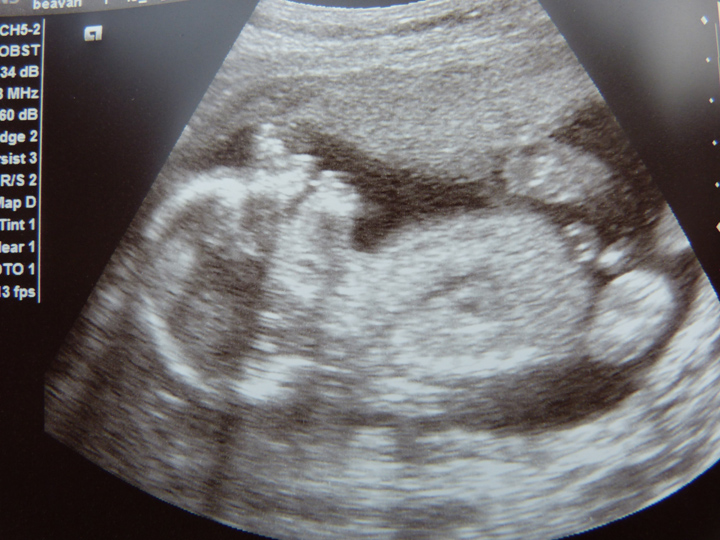

19 weeks u/s

The tech said def 100% boy and that the umbilical cord was going straight up, I'm sure they are right but I can't help grasping at straws a little. Please tell me not to be mental and of course this is another boy...

Attachment 6455

Thanks Rockstar, in the second picture the tech put an arrow pointing at the boy bits, and in the third picture I think the winky is the bobbly bit inbetween the legs but I'm confused as there are kind of two together and then a third mark to the right. Maybe that is part of the foot or something else?

I was really hoping for a clear potty shot but she didn't really understand what I mean and the only pictures we saw were sideways ones

I see a side view of boy parts in the 2nd pic. Congrats!

That's a boy without a doubt! Nice side view of boy bits (scrotum and penis)!!